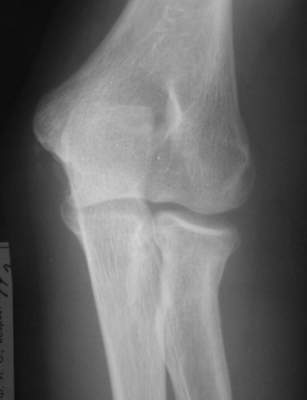

Есть методика воздействия на дистальный отломок при фиксации головки на месте - у нас - по-Марксу, у "них" - по-Паттерсону (ежели не обшибся с фамилией)...Есть методика прямого воздействия на проксимальный фрагмент... Путем пальцевого давоения... Вроде бы по-Ворохобову... у нас... Также делают и у "них"...Есть и как бы "промежуточная" методика в виде "давления" в сочетании с "накатом" - описана в каком-то вольюме JBJS, вроде бы израильскими (?)авторами...А есть еще метод по-Свинухову...Аналога у "них" мне не известно...О чрескожных манипуляциях спицами сознательно не упомянаю...Что предпочитаете?-------------------------А вот case report...Подросток 14 лет...Зкрытая репозиция "давление-накатом"... Безрезультатно...Через 3 дня репозиция по-Свинухову...Вроде бы все закончилось успешно...Однако 6 мес спустя после 2-кратного курса реабилитации клническая картина достаточно плачевна:Ротация предплечья:справа (здоровая) - 80 кнутри и 85-90 кнаружислева (больная) - 40 кнутри и 40 кнаружи При этом клинически внутренняя ротация справа (здоровая сторона) и слева (больная сторона) составляет порядка 85 и 80-75 соответвенно, но за счет ротационной мобильности запястья, порядка, например, 40-35 градусов на больной стороне...Сгибание слева (травмированная сторона) - 90 гр.разгибание - около 160 гр.Рентгенологически:в боковой проекции гетеротопическая оссификация по передней поверхности локтевого сустава, над головкой луча с "шипом" над радиокапителлярным сочленением...однако в прямой проекции локализация оссификата трудно определима, хотя вроде бы располагается по ходу сухожилия бицепса, т.е. в проекции луче-локтевого сочленения, но со стороны локтевой кости....Что делать?Кто виноват?:-)